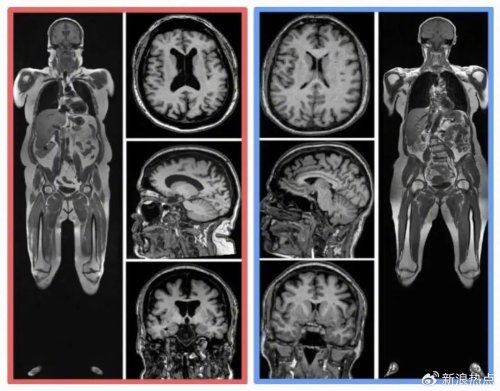

今年8月,来自美国华盛顿大学等10个科研机构,纳入了10,001名参与者,经过全身核磁、计算机深度学习、回归分析等一通复杂操作后,谨慎得出了结论:内脏脂肪越多,大脑(灰质、白质等)越小。